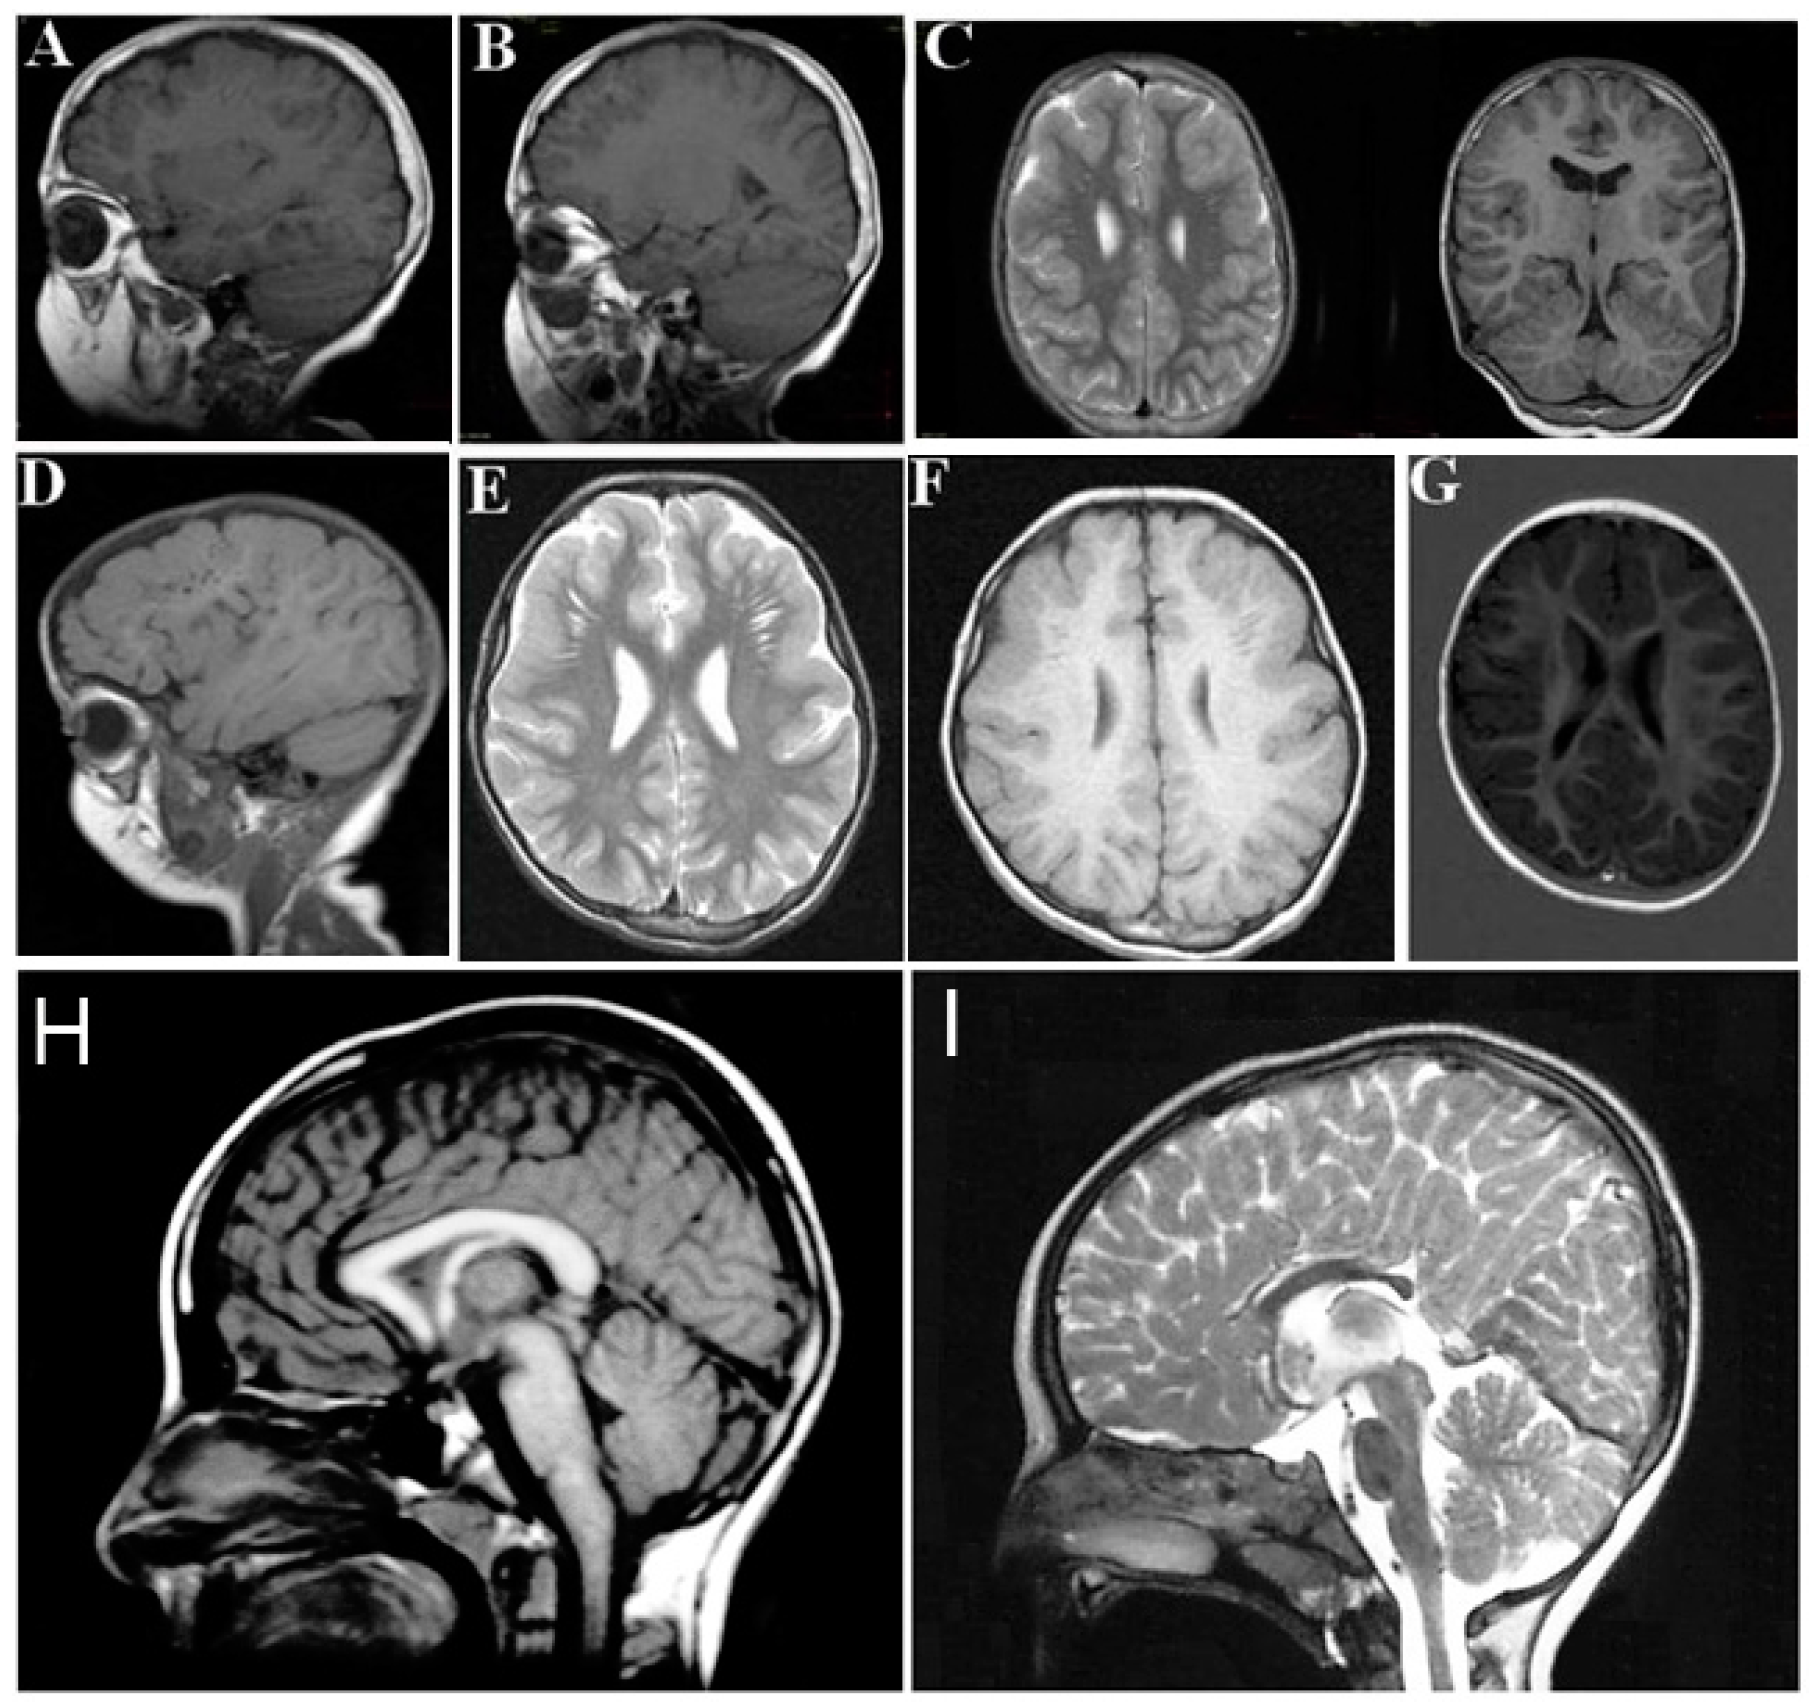

The neurological findings common to ARCL2A and ARCL2B patients are intellectual disability, hypotonia, psychomotor retardation, microcephaly, and seizures. Patients with GO, however, only demonstrate hypotonia if they demonstrate any neurological findings at all. Brain MRI imaging would be expected to differentiate between ARCL2A and ARCL2B based on the presence of cobblestone dysgenesis in ARCL2A compared to dysgenesis or agenesis of corpus callosum in cutis laxa IIB (Figure 4A–H) [2,5]. Brain MRI was not performed as part of this study and these features were not evaluated in our reported patients. Additionally, athetoid movements can occasionally be seen in ARCL2B and hearing loss has been reported in ARCL2A.

Figure 4.

(A,B,D) demonstrate frontal and frontotemporal cobblestone-like brain dysgenesis on lateral T1 weighed images in three patients with cutis laxa IIA. Note the enlarged Virchow space under the abnormally-developed brain region; (C,E,F) shows sagittal images of fronto-temporal cobblestone-like brain dysgenesis on T2 and T1 weighted images in the same patients; (G) sagittal image showing mild, frontal cobblestone-like brain dysgenesis; (I) control showing normal-sized corpus callosum; and (H) agenesis of the corpus callosum in a cutis laxa IIB patient.